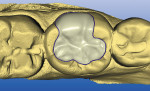

After local anesthesia was administered, the cavity was prepared for the nano-ceramic onlay, which was more conservative than for CAD/CAM ceramic onlays, with 1.5-mm reduction over the cusps and 1-mm axial reduction to ensure adequate restorative material to resist fracture. The proximal contacts of the tooth were maintained intact, as the marginal ridge areas were well supported by dentin and the proximal surfaces were free of caries (Figure 3).

Digital scans of the preparation quadrant and opposing teeth were made with the CEREC AC system, and the virtual models were aligned with a buccal scan. The preparation details were easily visualized on the virtual model in the design software (Figure 4). The restoration proposal was calculated based on the unique anatomy of the adjacent teeth, refined with the CEREC 3D V3.84 software program (Sirona) and transmitted to the milling chamber (Figure 5). A Lava Ultimate I14 block (shade A2 LT) was inserted into the milling chamber, and the onlay was milled from the prefabricated block of nano-ceramic (Figure 6). Upon recovery of the milled restoration from the milling chamber, the restoration was tried in and adjusted for optimum internal adaptation and marginal fit to the cavity preparation.